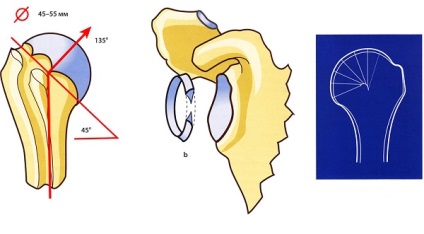

Szintén fontos szerepet játszanak a stagnáló előrejelzések az ízületek körül. Fő feladatuk - korlátozását tartományban mozog. Példaként nézd meg a vállát. A felkarcsont a csont dudor. Mivel a helyszín mellett a kinövést a penge, csökkenti a mozgási tartományát a kezét.

- Gömbcsukló - a felület alakja van golyó (egy domború, a másik homorú), amelyben az emberek, hogy a körkörös mozgás. Alapvetően forgás jön létre három egymásra merőleges tengely, a metszéspont a központja a fej. A különlegessége a nagyon kis számú kötegek, amely nem akadályozza a körkörös forgás.

- A csésze alakú - feltételezi egy anatómiai nézete egy mély üreg egy csont, amely kiterjed a legtöbb területen a második felület a fej. Ennek eredményeként kevesebb szabad mozgását, mint gömbalakú. Annak szükségességét, hogy nagyobb fokú ízületi stabilitást.